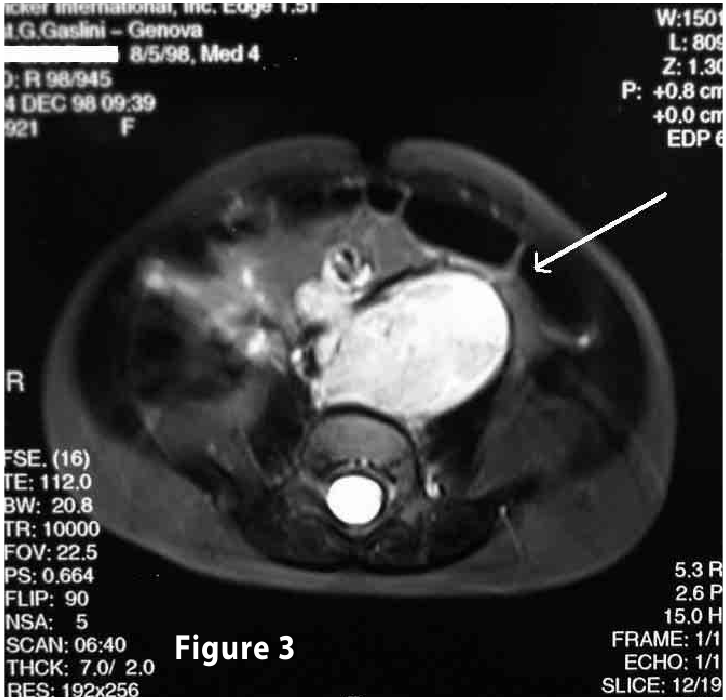

Complete objective response of neuroblastoma to biological treatment.

Figure3